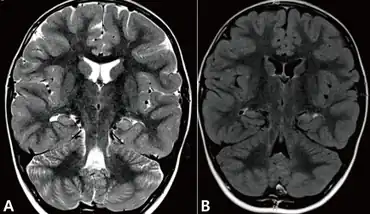

| Coronal sections of brain magnetic resonance imagings taken just after the person's fourth prolonged autonomic seizure. Slightly increased signal intensity on the T2 a) and fluid-attenuated inver sion recovery image b) were observed. Structures of the left hippocampus are less obvious than the right. | |